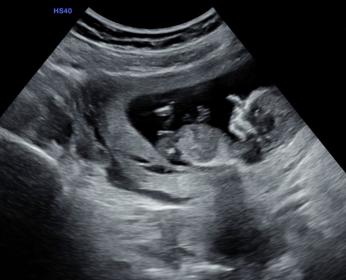

Today I had my 12 week scan. I already have 2 sons (8 and 9 years old) and we are hoping for a girl this time.

Tech couldn't see anything with the pottyshot, but is there a clue with NUB?

I'm not even sure I see a nub, sorry. I think *if* that's a little bit of the nub sticking out, I'd slightly lean boy since it looks angled. Again though, I'm not sure. Hopefully I'm wrong and it's a girl!